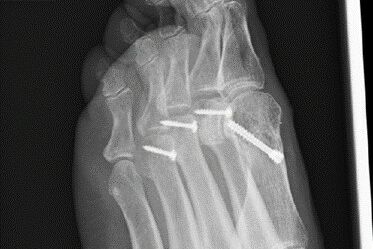

Therapie: distale Umstellung am MT1, Osteotomie an MT 2-4

Die operative Korrektur, bei der Umstellungsosteotomien an den Mittelfußknochen 1-4 links durchgeführt wurden, erfolgte im Mai 2018.

Bei anhaltenden Beschwerden wurde im Mai 2019 eine Röntgenaufnahme durchgeführt, die einen Schraubenüberstand von 1mm am Köpfchen des MT3 ergab. Dieser Befund wurde durch eine CT Untersuchung, bei der zusätzlich eine Arthrose im Grundgelenk der Großzehe und der zweiten Zehe gefunden wurde,  bestätigt.

Der Schraubenüberstand sei auf der postoperativen Aufnahme, die nicht streng seitlich gewesen sei, nicht erkennbar gewesen.